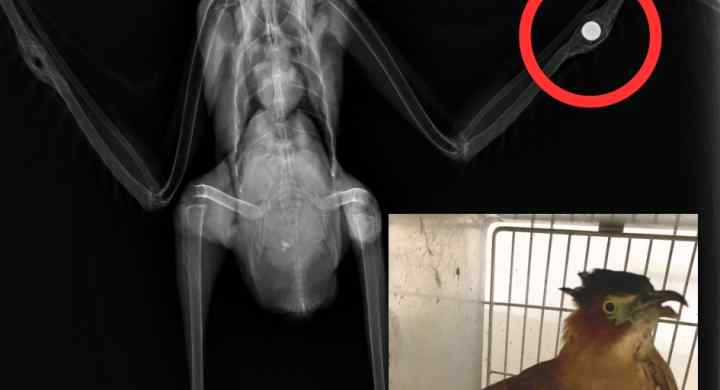

拒絕二次毒害:台北市是鳳頭蒼鷹與領角鴞等猛禽穩定築巢繁殖的家園,不當投藥將透過食物鏈毒殺猛禽,摧毀都市生態系。